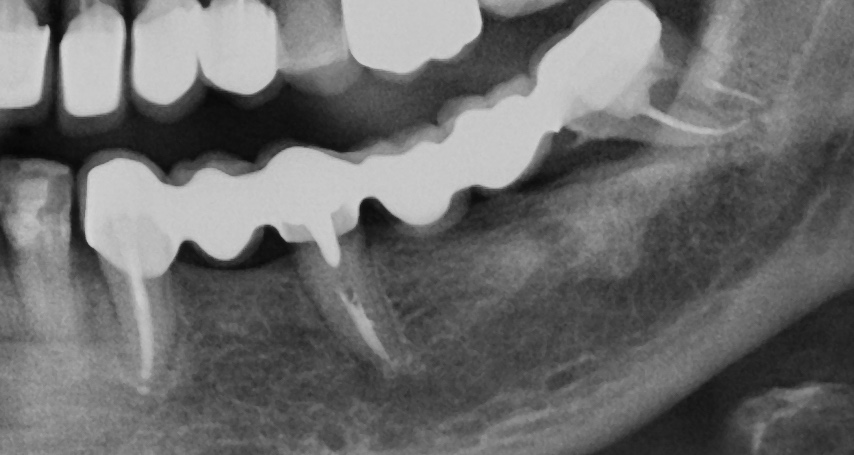

Σε περιπτώσεις που έχει χαθεί σημαντική ποσότητα οστού ή υπάρχει ατροφία των ούλων, μπορεί να χρειαστεί οστική αναγέννηση ή τοποθέτηση μοσχεύματος (bone graft / soft tissue graft).

Αυτές οι επεμβάσεις πραγματοποιούνται πριν ή ταυτόχρονα με την τοποθέτηση του εμφυτεύματος, ώστε να εξασφαλιστεί η σταθερότητα και η αισθητική του αποτελέσματος.